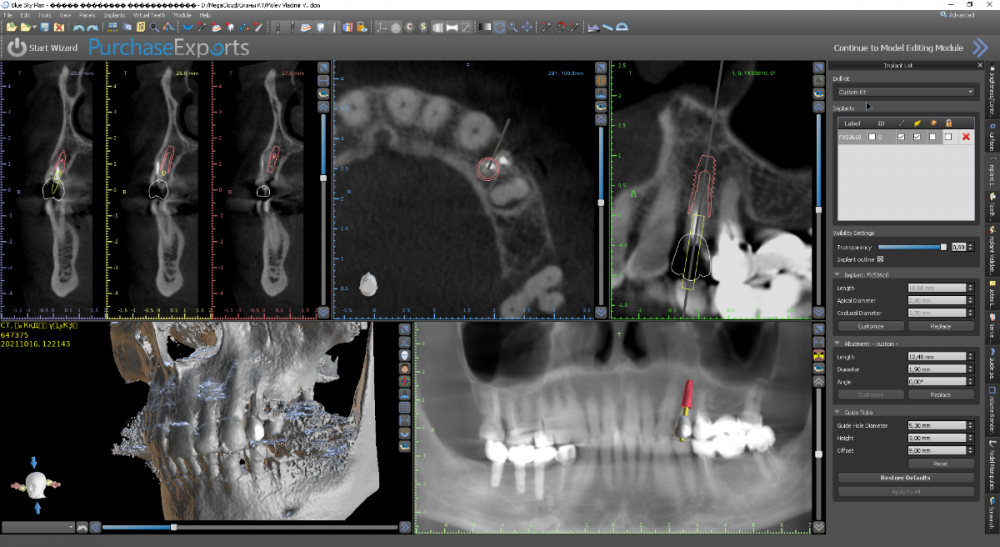

Женька Опубликовано 21 октября, 2021 Автор Поделиться Опубликовано 21 октября, 2021 Хотя если планировать вот так, то вроде и не всё так уж страшно? Ссылка на комментарий

Женька Опубликовано 27 октября, 2021 Автор Поделиться Опубликовано 27 октября, 2021 @Фаик Исламбеков пока только получил согласие пациента на снятие моста, одномоментную установку вот в таких позициях. Буду делать одномоментно, факап может только с 2.7 случиться кмк... в случае чего ушьём и зайдем через 2-3 месяца. 1 Ссылка на комментарий

Женька Опубликовано 11 января, 2022 Автор Поделиться Опубликовано 11 января, 2022 Как я и говорил? купил объектив, теперь буду больше своих косяков фотографировать и выкладывать. Наконец-то руки дошли и машина доехала обратно до Башкирии и прооперировал пациента. Аккуратно сняли мост путём отпиливания по коронкам, удалили зубы достаточно быстро. Долго ловил пилотной фрезой дентиум правильное положение... так и не поймал. Вспомнил как Пётр Лазукин использует фрезу на турбинке для пилотного сверления и о чудо, сразу появилось устойчивое направление и линдеман перестал соскакивать, спасибо за видосики Петру Ну и далее по протоколу, пилотное положение 2.4 и 2.5 менял по 3 раза каждый (а в итоге всё равно не доволен получившимся направлением и судя по всему слишком близко) 2.7 с синуслифтингом. В лунки A-oss, сверху мембрана от Владмивы. И заживление через 9 дней. К сожалению, фото швов и той порнографии, что была сделана с лунками и мембраной нет. Резюмируя, это были 35-38 имплантаты которые я поставил, я уже чувствую себя намного увереннее (когда как Пётр турбиной пилотную точку сделал вообще в себя поверил ), но проблемы с позиционированием ещё долго будут меня преследовать. Жду критику и помидоры за РГ контроль. Ссылка на комментарий